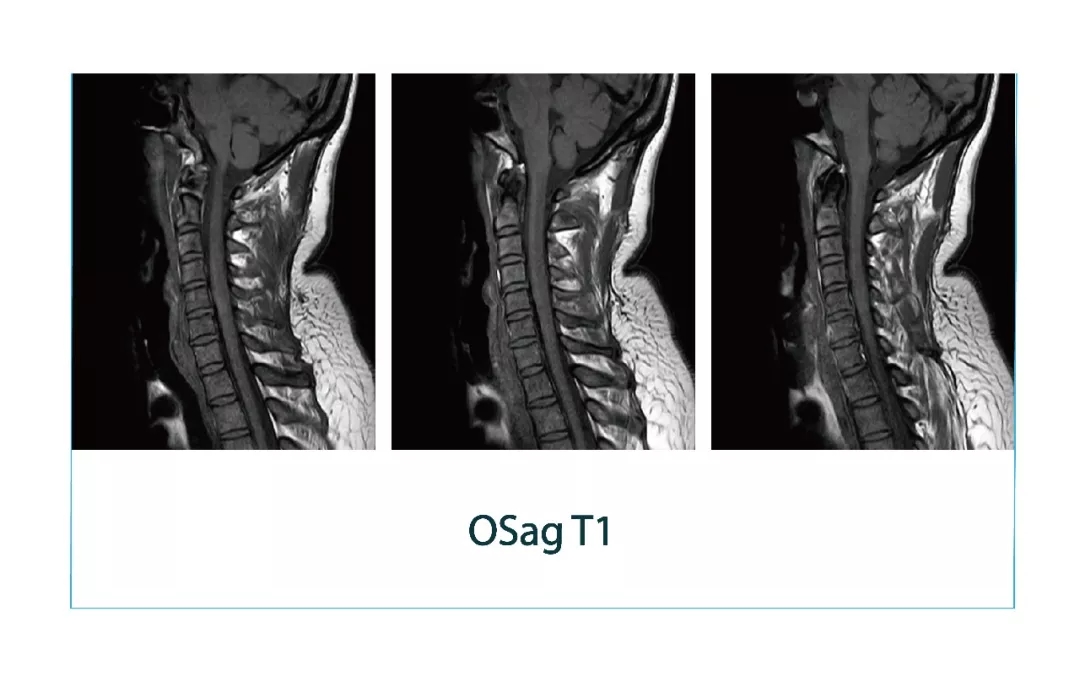

【朗润影像档案】磁共振影像病例分享(编号20180330)